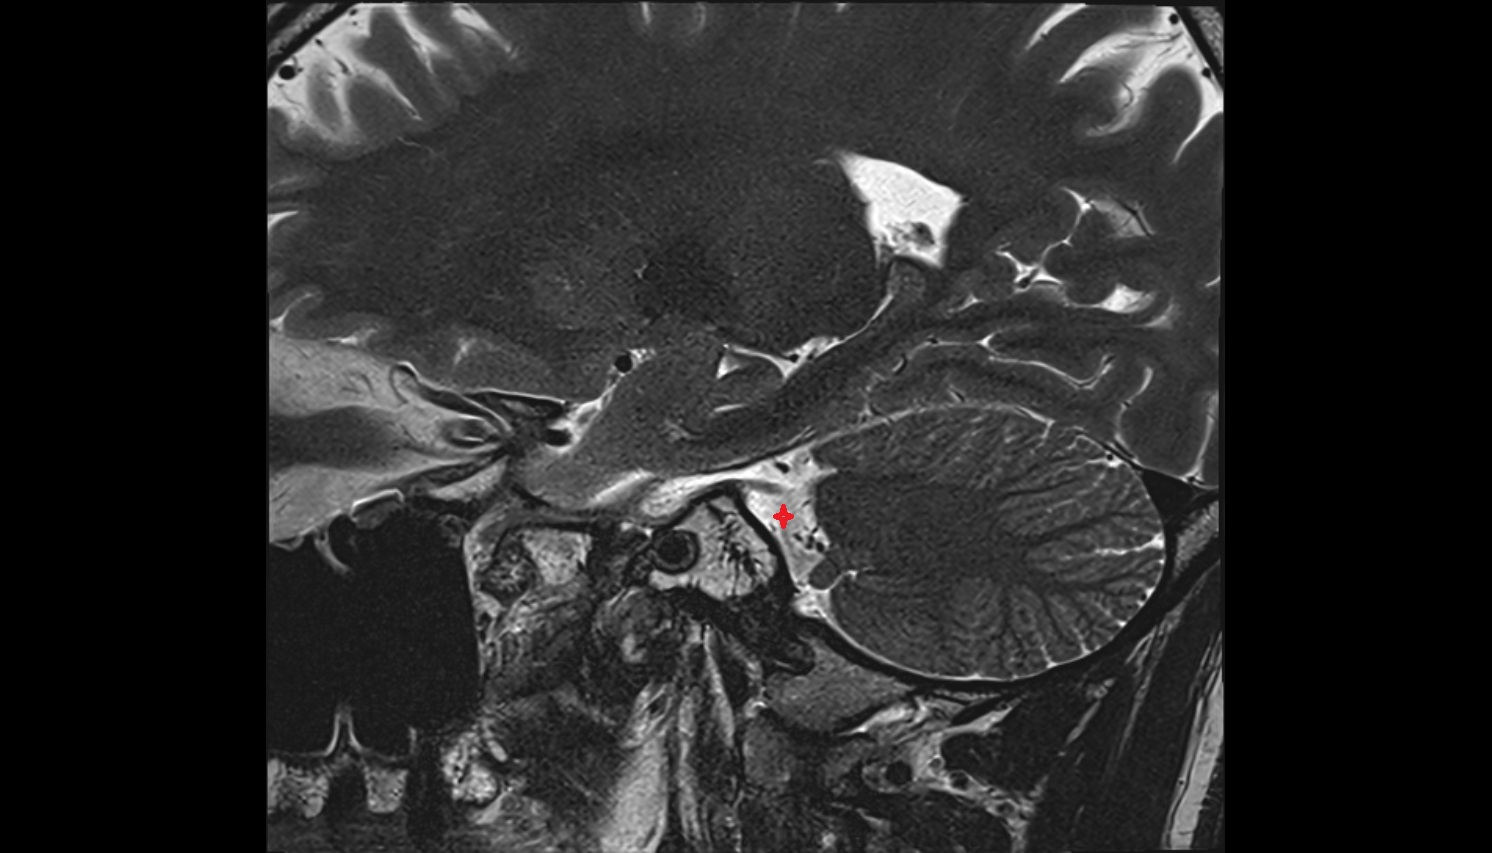

- Temporomandibular joint

- Mandibular condyle

- Mandibular fossa

- Articular disc of temporomandibular joint

- Articular eminence

- Articular surface of mandibular fossa

- Intermediate zone of articular disc